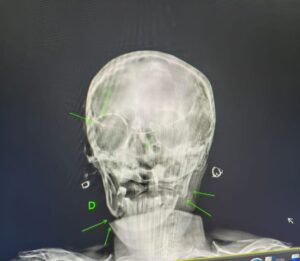

De acordo com boletim de ocorrência, D. G.S.N, de 29 anos, agrediu a mãe de 55 e o irmão dele de 21. De acordo com boletim de ocorrência registrado na Central de Polícia Judiciária, a Guarda Civil Municipal foi acionada para atender uma confusão entre familiares. Quando os guardas chegaram ao local, encontraram uma ambulância socorrendo a mulher de 55 anos. A mulher apresentava sangramento e graves lesões. Na casa também estava o agressor e o irmão de 21 anos. O rapaz de 21 anos estava muito abalado e contou, que ele e o irmão estavam brigando, a mãe teria tentado apartar a briga e teria sido violentamente agredida pelo filho de 29 anos. O rapaz de 21 anos disse que também havia sido agredido pelo irmão de 29. , D. G.S.N, teria usado um objeto contundente para agredir a mãe. O acusado admitiu ter agredido a mãe e também o irmão. Alegando, contudo, ter utilizado as próprias mãos e também um rodo. A vítima foi encaminhada ao hospital municipal de Ibaté, onde foi constatado quadro clínico grave, com fraturas na região do maxilar, clavícula e região occipital, permanecendo impossibilitada de prestar declarações. Devido à gravidade das lesões, a mulher foi transferida para a Santa Casa de São Carlos. A ocorrência foi apresentada na Central de Polícia Judiciária de São Carlos, onde o detido foi autuado em flagrante por lesão corporal e tentativa de homicídio e recolhido ao Centro de Triagem de São Carlos.

Foto das lesões da vítima.